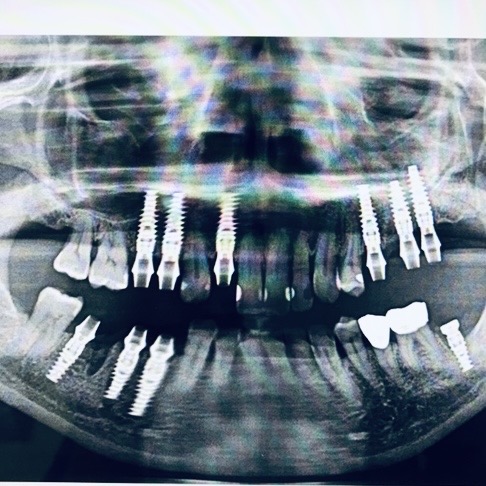

- ●得意とされるのは咬合再構成・骨造成・オールオン・ザイゴマ等の難症例

オールオンも上顎両サイドに2本足して、上6下4の10本埋入を得意とされています。オールオンの症例が年間100症例ほど、ザイゴマインプラントは年間100本ほどで、全国でもトップクラスの先生です。

吉留先生のサンプル症例

こちら↓に先生の症例をサンプルとして、説明と一緒に掲載してあります。ご一読ください。